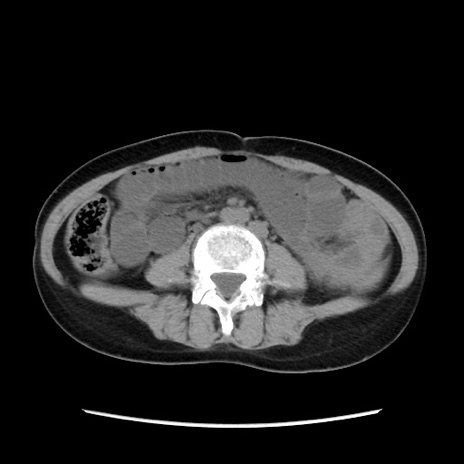

症例32(横断像)

【症例】40歳代 女性

【主訴】上腹部痛、嘔気・嘔吐

【現病歴】約9時間前頃から急に上腹部痛、嘔気、嘔吐が出現。改善しないため救急要請。

【既往歴】子宮頚癌(広汎子宮全摘術、放射線療法)、腸閉塞

【身体所見】腹部:平坦、軟、腸雑音亢進、上腹部を中心に腹部全体に圧痛あり。

【データ】WBC 8400、CRP 0.03